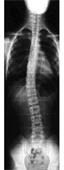

Une scoliose est une déviation permanente de la colonne (rachis) avec rotation vertébrale.

Dans le plan frontal (appelé aussi coronal), la colonne vertébrale (rachis) est parfaitement rectiligne sur un bassin bien équilibré.